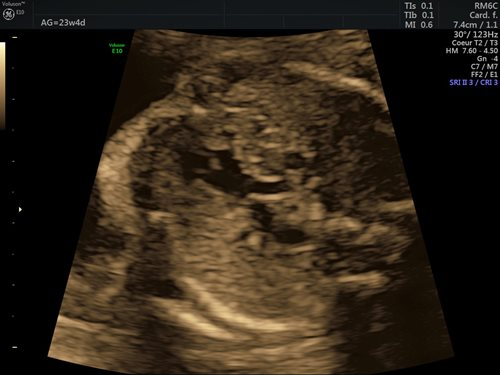

Dans la grande majorité des cas (90 %), l’étiologie des cardiopathies congénitales est multifactorielle, un facteur de risque classique comme des antécédents familiaux au 1er et 2e degré, la présence d’une anomalie chromosomique, d’un diabète maternel de type 1, d’une phénylcétonurie, la prise de certains médicaments ou une infection n’étant pas retrouvé. Pour cette raison, un dépistage systématique par échocardiographie foetale reste indispensable, idéalement entre 18 et 22 semaines de gestation. Le dépistage recommandé consiste en l’obtention d’une vue des 4 cavités cardiaques (fig. 1) et d’une vue des voies d’éjection (fig. 2). (2)

Figures 1